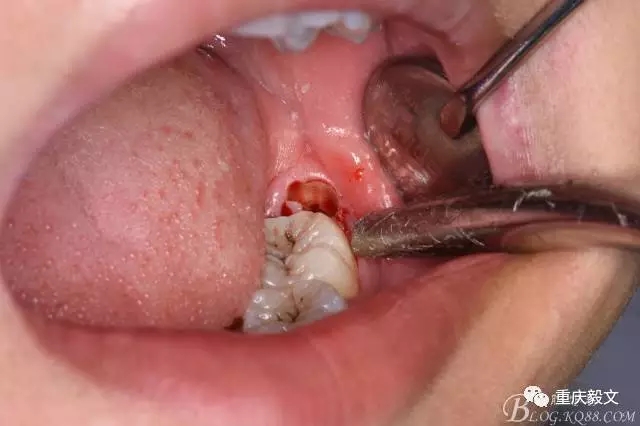

圖5.分離舌側(cè)牙齦

圖6.分離頰側(cè)牙齦,目的使牙冠和牙根能順利從牙齦軟組織脫位。